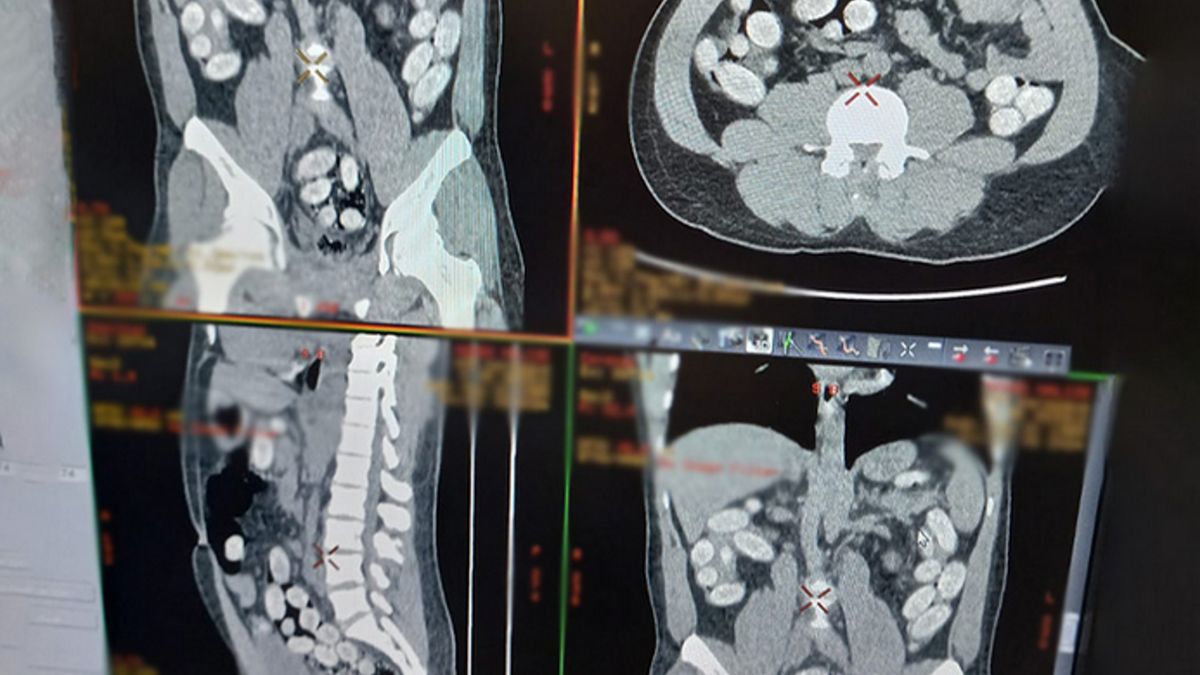

Wyniki tomografii komputerowej przewodu pokarmowego potwierdziły wewnątrzustrojowy przemyt środków odurzających. 35-latek w swoim organizmie przemycał w kapsułkach prawie 1,2 kg narkotyków.